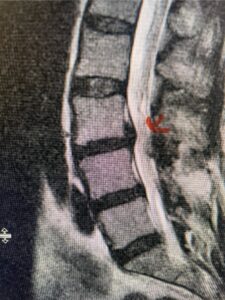

This 54-year-old morbidly obese female presents with progressive back and leg pain and quadriceps weakness. She had no diabetes. She failed all means of conservative management including physical therapy and epidural injections. On imaging she had severe stenosis at L3-4 with a disc protrusion and a slight grade 1 spondylolisthesis at L3-4 (Fig 1). We performed dynamic lumbar x-rays which demonstrated instability at L3-4 and L4-5 (Fig 2). The patient wished to have surgery. We performed an L2-4 decompressive laminectomy and L3-5 in situ fusion because of her instability. Post operatively the patient had relief of leg pain, although the patient was slow to mobilize.

Figs. 1a: Sagittal lumbar T2-weighted MRI demonstrating severe lumbar stenosis with a slight grade 1 at L3-4 and a disc protrusion (red arrow )